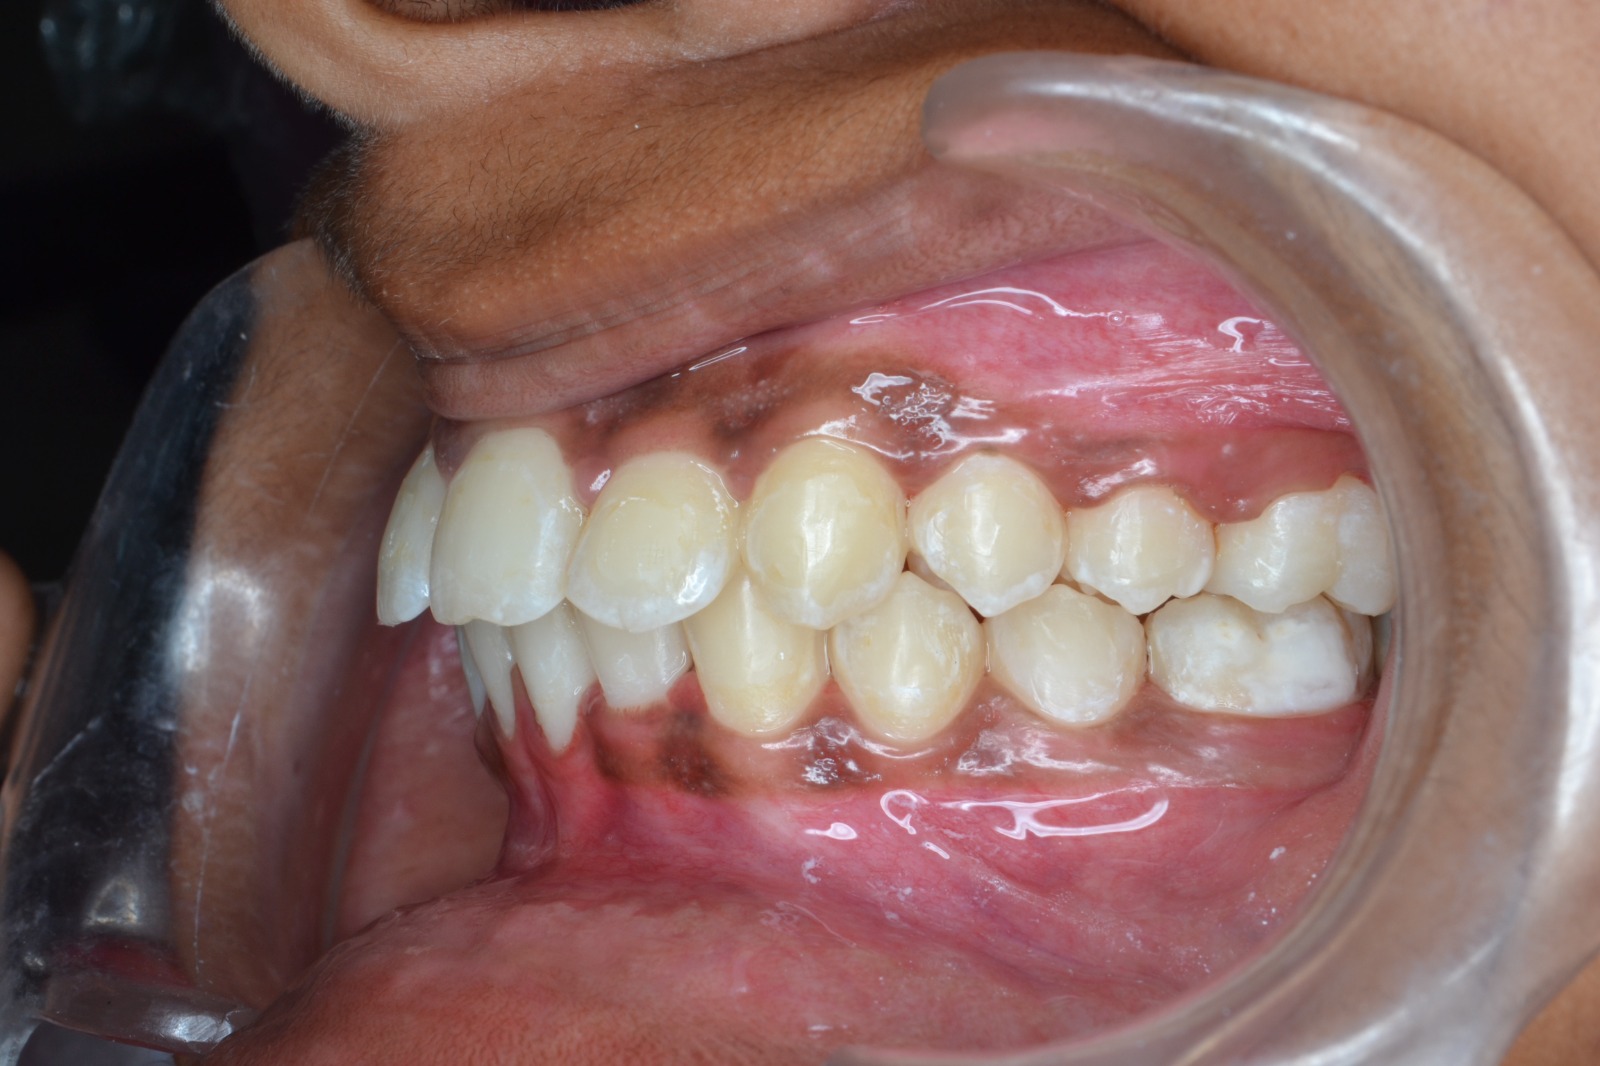

After/Before

See stunning smile transformation before and after

Before After